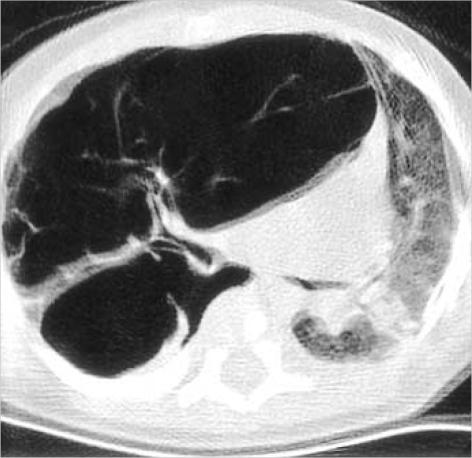

Lymphangioma is an abnormal collection of lymphatics that are developmentally isolated from the normal lymphatic system. Lymphangioma rarely presents as a solitary pulmonary lesion. We report a rare case of intrapulmonary cystic lymphangioma involving the upper lobe of the right lung, which presented with dyspnea in a 2-month-old infant. High-resolution computed tomography (HRCT) of the chest demonstrated a well-circumscribed, multiseptate, cystic lesion in the upper lobe of the right lung, mimicking the feature of type I congenital cystic adenomatoid mal-formation. The tumor was removed by bilobectomy of the upper and middle lobes of the right lung, and its pathologic examination confirmed the diagnosis of an intra-pulmonary cystic lymphangioma.

淋巴管瘤是淋巴管的异常聚集,在发育上与正常淋巴系统隔离。淋巴管瘤很少表现为孤立的肺部病变。我们报告一例罕见的右肺上叶肺内囊性淋巴管瘤病例,该病例发生在一名2个月大的婴儿身上,表现为呼吸困难。胸部高分辨率计算机断层扫描(HRCT)显示右肺上叶有一个边界清晰、多分隔的囊性病变,类似I型先天性囊性腺瘤样畸形的特征。通过右肺上叶和中叶双叶切除术切除肿瘤,病理检查确诊为肺内囊性淋巴管瘤。